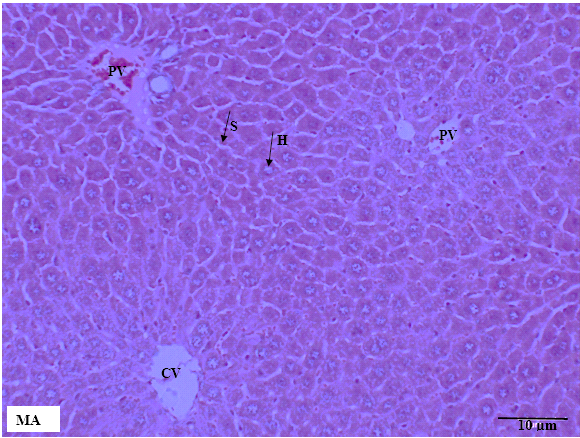

The results obtained from liver and kidney tissues are summarized in table 6. No significant gross changes were detected in liver and kidneys tissues in all groups and across both sexes (fig. 3 to fig. 6). Inflammatory cell infiltration, necrosis, and hemorrhage were absent in the treated animals. There were also no changes observed in the central vein, portal vein, hepatocytes, sinusoids, and bile ducts. There were no changes in the structure of kidneys with respect to glomeruli, distal and proximal tubules. The scoring of liver and kidney tissues were made by a pathologist who was blinded to the treatment groups.

Tissue changes were not detected in the control group.

Fig. 3: Liver tissue in male mice across treatment groups. MA: male control group, MB: male mice treated with 1000 mg/kg MECN, MC: male mice treated with 2000 mg/kg MECN. No cellular structural changes were detected in both the treated and control groups. H: hepatocytes, S: sinusoids, PV: portal vein, CV: central vein. (HandE staining, scale bar =10 µm, original magnification x200)